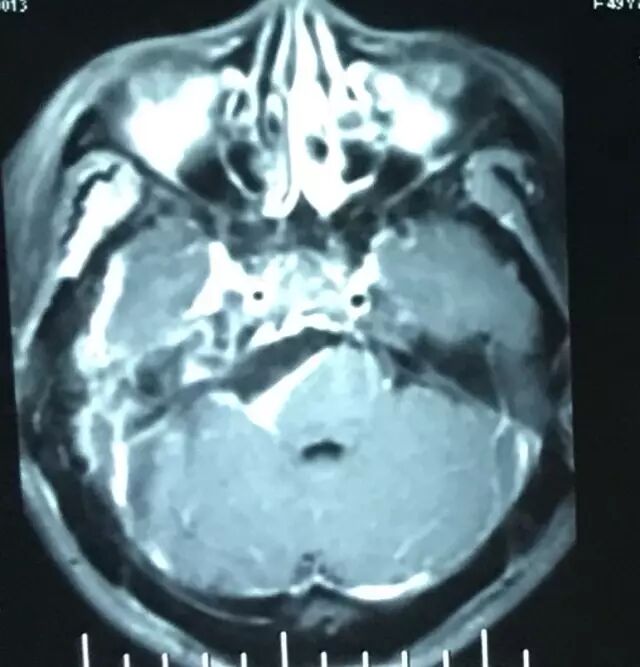

查体:神清语利,双瞳等,光反应灵敏,右侧面部浅感觉减退,行走不稳,四肢肌力基本正常。核磁共振检查见右侧岩斜区肿瘤,考虑岩斜脑膜瘤。

肿瘤强化明显,部分侵入海绵窦。

术后MRI T2加权像

术后MRI T1平扫,复查可见明胶海绵影(高信号)。

术后MRI增强核磁扫描